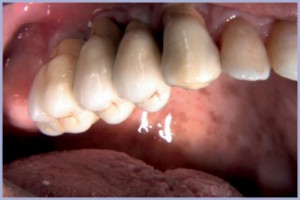

Gli accessi transmucosi agli impianti appaiono precisi nelle loro caratteristiche (fig. 24).

- Fig. 24